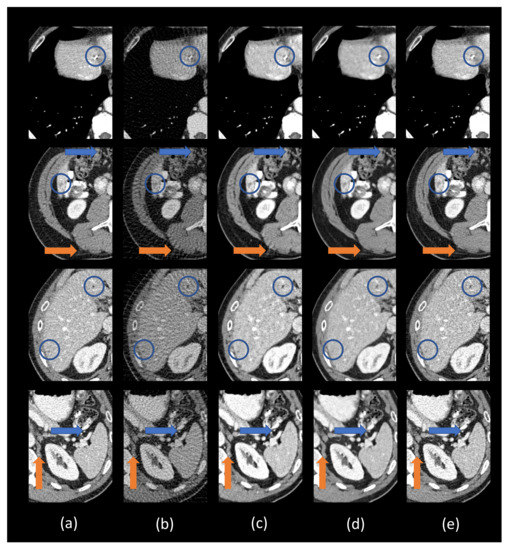

3.3. Comparison with Other Deep Learning Methods

3.4. Ablation Analysis